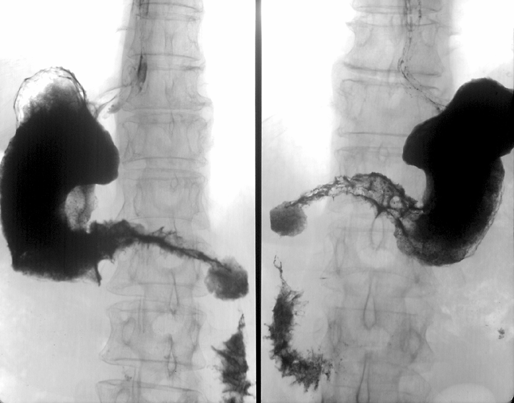

Наиболее часто встречается ;рак антрального отдела ;желудка (рис. 2) и пилорического канала — более 40%.

Рисунок 2. Рак антрального отдела желудка

Второй по частоте — рак ;тела желудка либо антрального отдела с распространением на тело ;— около 30% наблюдений.

Вдвое реже отмечается рак ;проксимального отдела желудка, часто с распространением инфильтрации на н/3 пищевода — т.н. ;кардио-эзофагеальный рак ;(рис. 3) — его частота не превышает 20%. Следует отметить, что в последние два десятилетия эпидемиологи, в основном в Западном полушарии, отмечают увеличение частоты рака проксимального отдела желудка с распространением на пищевод (рис. 4) и снижение частоты рака дистального отдела желудка (Yoshida S., Yamaguchi H. et al., 1993). Этот феномен до сих пор не нашел достаточного теоретического обоснования, однако, является общепризнанным фактом. В некоторой степени снижение частоты рака дистального отдела желудка может быть связано со снижением уровня инфицированности населения ;H. pylori ;(возможный этиологический фактор). Чаще рак желудка возникает на малой кривизне — 20–25% и значительно реже на большой — около 3%. Относительно часто (более 2%) в желудке отмечается мультицентрический рост опухоли, что косвенно подтверждает ;теорию опухолевого поля.

Рисунок 3. Рак проксимального отдела желудка

Рисунок 4. Рак проксимального отдела желудка с переходом на пищевод

Согласно большим статистическим исследованиям, более благоприятный прогноз при раке дистального отдела желудка — 5-летняя выживаемость превышает 30%. Промежуточное положение занимает рак тела желудка — выживаемость несколько ниже, чем при раке антрального отдела — от 25 до 30%. Наименее благоприятно протекает рак проксимального отдела желудка, особенно при распространении инфильтрации на пищевод — выживаемость около 20 и 15% соответственно.